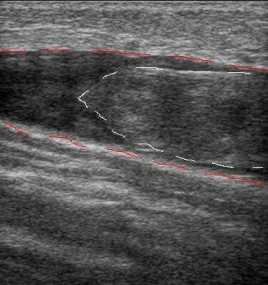

пациентов с большим весом, у которых бедренная вена в Гунтеровом канале не лоцируется. В норме в

венах не должно быть включений, только клапаны в виде двух движущихся при дыхании пластин, в виде

колышашихся парусов прерывают венозный просвет. Очень наглядно видна работа клапанов при

функциональных пробах и цветовом кодировании кровотока, когда в норме цвет исчезает, а при

несостоятельности клапана он меняется на противоположный.